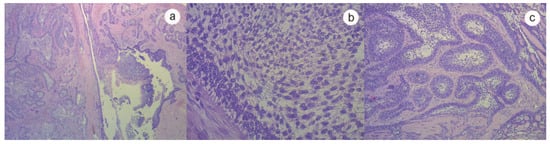

:Case History